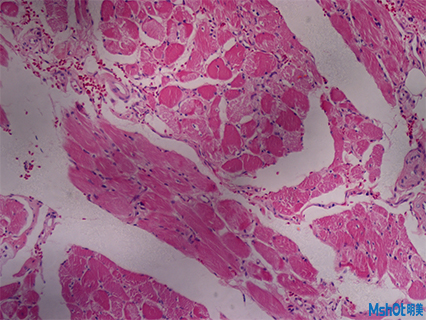

病理切片取一定大小的病变组织,用病理组织学方法制成病理切片。病理切片是透明的,在显微镜下能够观察到组织的形态,搭配显微镜相机可对观察到的形态效果图进行保存对比,拼接等操作,通过病变的发生发展过程,作出病理诊断。

近日,深圳某医疗科技公司在网上找到我们,客户已有一台奥林巴斯倒置显微镜IX71,需要配一套高像素显微镜相机拍病理切片和荧光切片,深圳区域工程师根据老师实际需求推荐了明美科研级显微镜相机MSX2,这款显微镜相机采用大靶面高性能的成像芯片,设计USB3.0数据传输接口,具有高分辨率、颜色还原准确和高灵敏度的特点,其色彩表现,是液基细胞分析、免疫组化、骨髓细胞分析等对颜色要求高的病理诊断的理想工具。此外在明暗场、相衬、偏光、DIC、荧光成像等领域同样适用。